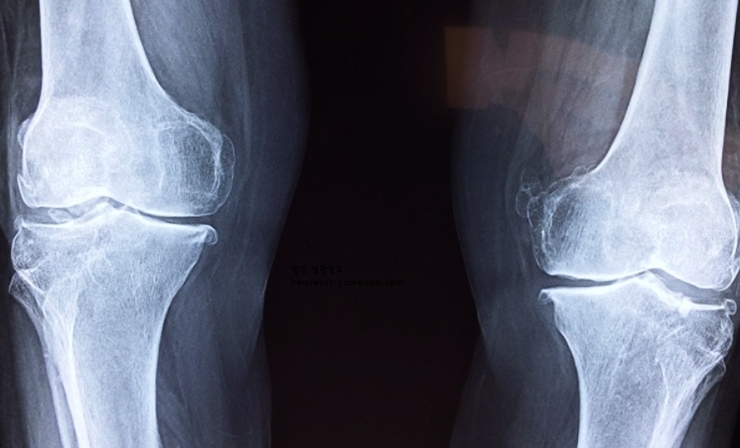

1. 퇴행성 관절염

원인으로는 퇴행성 관절염은 나이가 들면서 관절 연골이 닳아 발생합니다. 무릎 관절은 체중 부하를 많이 받는 부위라 손상이 쉽게 옵니다.

증상으로는 초기에는 가벼운 통증이나 시큰거림이 느껴지다가, 점차 통증이 심해지고 움직일 때 소리가 나는 경우가 많습니다. 날씨가 습하거나 추운 날에 증상이 악화되기도 합니다. 체중 감량, 규칙적인 운동(저충격 운동: 수영, 걷기 등), 약물치료, 심한 경우 인공관절 수술을 고려해보는 것도 무릎이 시큰거리는 이유 고민을 해결 할 수 있겠습니다.